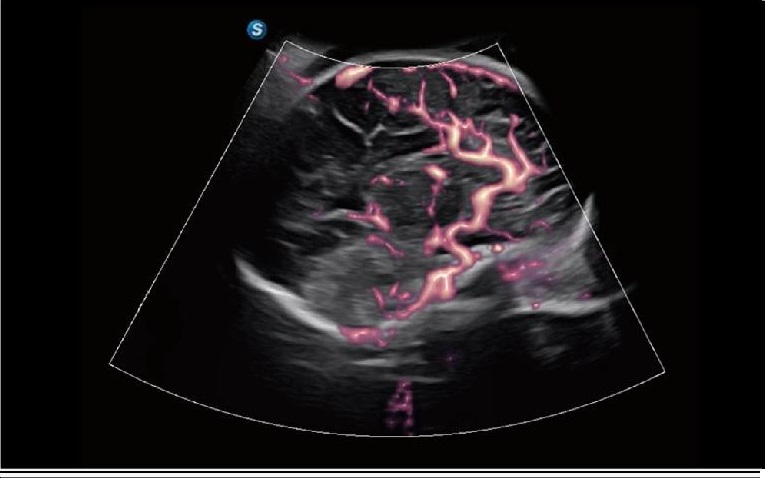

CEUS HFR

Yüksek Kare Hızlı CEUS (High Frame Rate CEUS), lezyonların perfüzyon sürecini ayrıntılı bir şekilde dinamik olarak görüntüler. MFI, MFI Time ve MFI Mix kombinasyonu, doktorların lezyon perfüzyonunu farklı açılardan görmesine olanak tanıyarak tanının daha kolay ve daha hassas bir şekilde konulmasını sağlar.